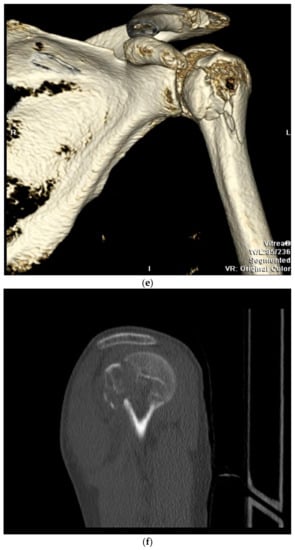

9. Open Reduction and Internal Fixation

11. Open Reduction Internal Fixation with an Intramedullary Nail